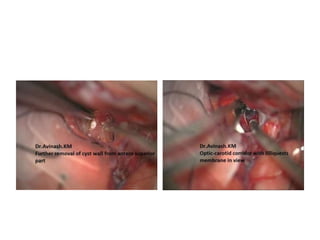

a,b Intraoperative image of the fenestration of deep cystic membrane using different microsurgical

instruments (forceps and scissors). Asterisks posterior communicating artery and anterior choroidal

artery. c Fenestration of the cisternal layer (cross Liliequist’s membrane). d Intraoperative picture at the end

of the procedure